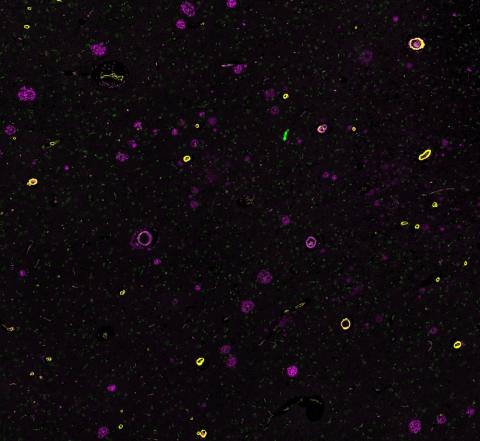

This research involves carrying out experiments to study the role in vascular dementia of blood flow changes, loss of blood-brain barrier (BBB) function, changes in the physical properties of blood vessels, loss of nutrient supply to brain tissue, and downstream effects on neuronal and glial cell function, including on myelin integrity.

Credit: Attwell Lab.